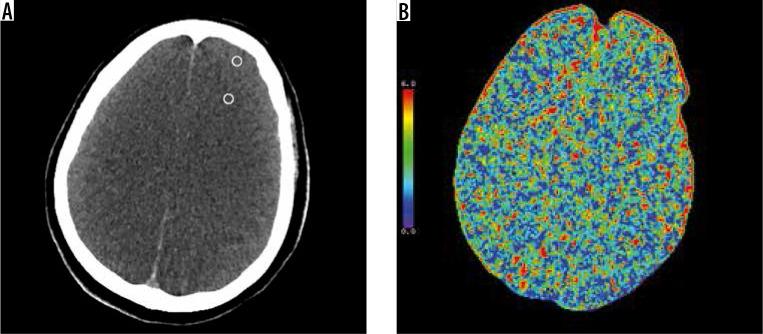

To assess the utility of brain parenchyma density measurement on unenhanced computed tomography (CT) in predicting brain death (BD), in order to evaluate the added value of CT perfusion (CTP).

MATERIAL AND METHODS

A total of 77 patients who were clinically diagnosed as BD and had both CT angiography (CTA) and CTP imaging in the same session were retrospectively reviewed. On unenhanced phase of CTA, density measurement was performed from 23 regions of interests (ROIs) which were located in the following areas: level of basal ganglia (caudate nucleus, putamen, corpus callosum, posterior limb of internal capsule), level of brainstem, grey- white matters on levels of centrum semiovale (CS), high convexity (HC), and cerebellum. CTP images were evaluated qualitatively and independently. Grey matter (GM), white matter (WM), density, and GM/WM density ratio of BD patients were compared with control subjects.

RESULTS

Comparing with the normal control group, the GM and WM density at each level and GM/WM density ratio of CS, HC, and cerebellum level were significantly lower in brain-dead patients ( = 0.019 for HC-WM, < 0.001 for other areas). Using ROC analysis, the highest value of area under curve (AUC) for the GM/WM density ratio was found at the HC level (AUC = 0.907). The sensitivity of the GM/WM density ratio at the HC level was found to be 90% when the cut-off value of 1.25 was identified. Evaluating the GM/WM density ratio together with the CTP results increased the sensitivity further to 98%.

CONCLUSIONS

The GM/WM density ratio at the HC level on unenhanced CT may be a useful finding to predict BD. Also, the addition of CTP increases the sensitivity of this method.

评估在未增强计算机断层扫描(CT)上测量脑实质密度对预测脑死亡(BD)的效用,以评估CT灌注(CTP)的附加值。

材料与方法

回顾性分析77例临床诊断为BD且在同一时间段内同时进行CT血管造影(CTA)和CTP成像的患者。在CTA的未增强期,从位于以下区域的23个感兴趣区(ROI)进行密度测量:基底节水平(尾状核、壳核、胼胝体、内囊后肢)、脑干水平、半卵圆中心(CS)、高凸面(HC)和小脑水平的灰质和白质。对CTP图像进行定性和独立评估。比较BD患者与对照组的灰质(GM)、白质(WM)密度以及GM/WM密度比。

结果

与正常对照组相比,脑死亡患者各水平的GM和WM密度以及CS、HC和小脑水平的GM/WM密度比均显著降低(HC-WM为P = 0.019,其他区域P < 0.001)。使用ROC分析,发现GM/WM密度比在HC水平的曲线下面积(AUC)最高(AUC = 0.907)。当确定截断值为1.25时,HC水平的GM/WM密度比敏感性为90%。将GM/WM密度比与CTP结果一起评估可使敏感性进一步提高至98%。

结论

未增强CT上HC水平的GM/WM密度比可能是预测BD的有用指标。此外,增加CTP可提高该方法的敏感性。